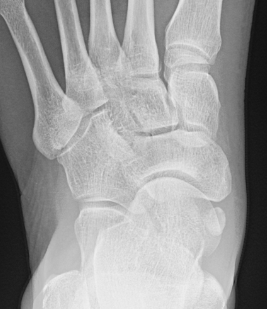

Classification

| Type I | Type II | Type III |

|---|---|---|

|

Small ossicle proximal to insertion In the Tibialis posterior tendon |

Triangular ossicle Connected to navicular via syndesmosis May fracture with injury |

Enlarged medial navicular Cornuate navicular Likely that Type II accessory navicular has fused |